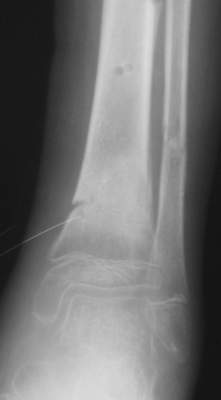

A> Перелом костей н\3 правой голени со смещением.

Это от 13.10.04? А это близкие к первичным снимки?

A> Перелом большеберцовой

A> кости можно охарактеризовать как компрессионно-оскольчатый.

A> В январе 2005: варусная деформация н\3 голени,

A> Операции: 1 Клиновидная резекция на вершине деформации м\берцовой кости.

A> 2 Тугоподвижный ложный сустав н\3 б\берцовой кости.

а был у больного перелом дистального метафиза большеберцовой с чисто

варусным смещением на фоне пластической деформации малоберцовой на том

же уровне и того же характера.

A>> Перелом костей н\3 правой голени со смещением.

AVM> Это от 13.10.04? А это близкие к первичным снимки?

Есть даже тень периостальной костной мозоли и сросшийся перелом

малоберцовой кости.

Это сросшийся перелом малоберцовой кости. И ложный сустав

н\3 б\берцовой кости.

Так как речь зашла непосредственно о травме, см этапные

снимки. Как все было

Первичные

Вытяжение

Фиксация

в гипсе

Промежуточный